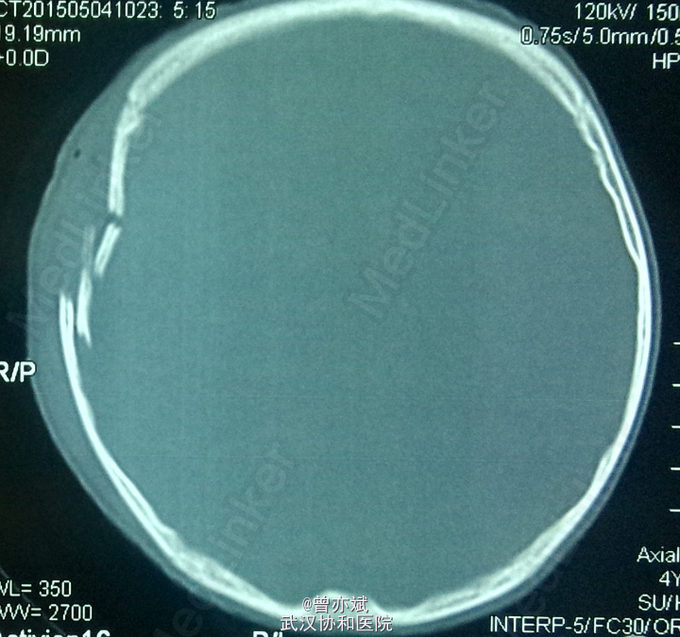

患者男 ,4岁。 因“头部外伤1天”入院,急诊行CT示:右侧颞顶骨额骨多发凹陷性骨折、颅内积气、脑挫裂伤,于急诊行头皮清创缝合。

查体:右侧颞顶部头皮软组织肿胀,清创缝合术后。于查体无特殊。CT如下

诊断:Ⅱ级脑外伤 右颞顶额骨凹陷性骨折 右侧颞顶部软组织损伤 处理:行保守治疗 。